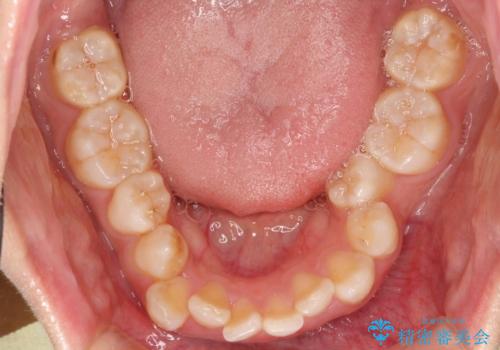

重度のガタガタのインビザラインによる非抜歯矯正

- 全体的なガタガタを気にされて来院されました。

抜歯矯正も考えられる状態でしたが、ご本人的になるべく歯を抜かない矯正を希望されました。

奥歯を後方に移動させるのと、歯と歯の間にわずかに隙間を作ることでスペースを確保して、抜歯をせず歯を並べる計画としました。

ガタガタの度合いが大きかったので少し時間がかかりましたが、非常に協力的な患者様でしたので、抜歯をせず計画通りに治療を終えることができました。